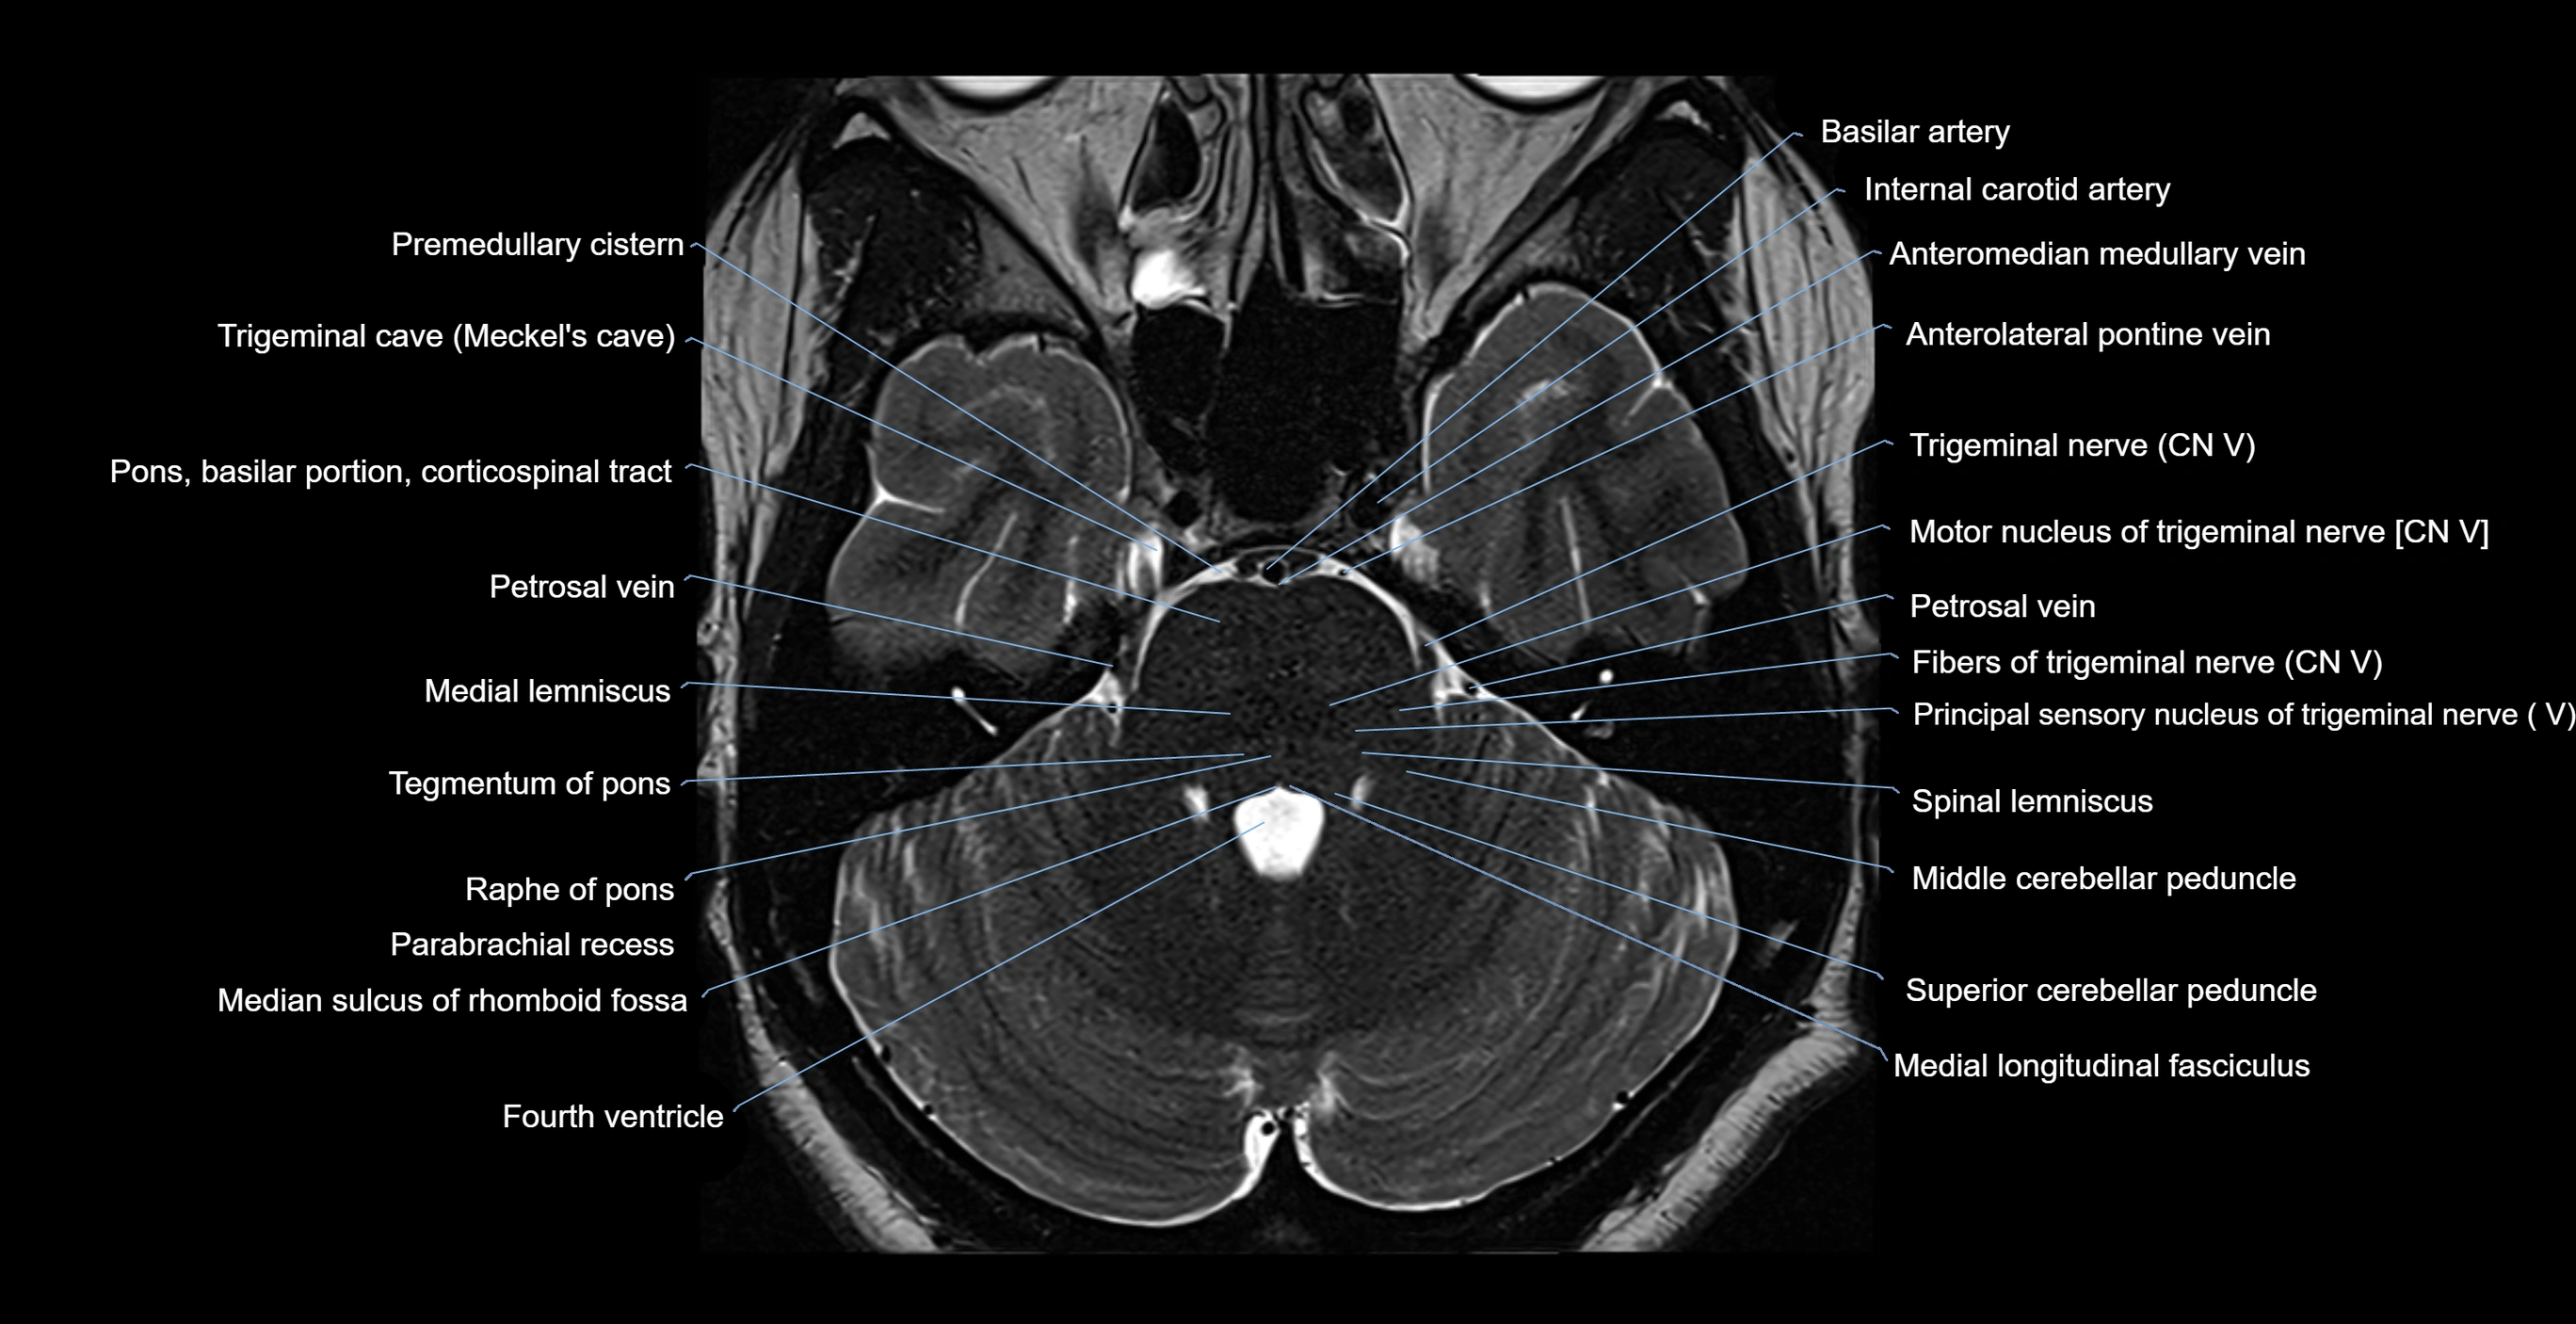

MRI images